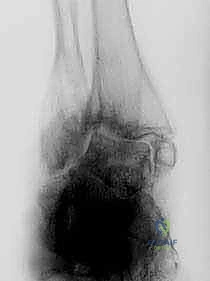

2. التصوير الطبي المتقدم

- الأشعة السينية (X-rays) أثناء الوقوف: وهي الخطوة الأهم لرؤية العظام تحت تأثير وزن الجسم. تظهر الأشعة اختفاء المسافة المفصلية، وتكوّن النتوءات العظمية، ودرجة التشوه المحوري.

- الأشعة المقطعية (CT Scan): ضرورية جداً لتقييم جودة العظام بشكل ثلاثي الأبعاد، وتحديد مدى التجاويف العظمية (Cysts) التي قد تحتاج إلى ترقيع عظمي أثناء الجراحة.

في الحالات المرضية المتقدمة التي يستهدفها هذا المقال، يكون التلف قد طال كلا المفصلين. الألم لا يأتي فقط من حركة القدم لأعلى ولأسفل، بل أيضاً من أي محاولة للتكيف مع الأرض. الغضاريف التي كانت تعمل كوسائد ملساء قد اختفت تماماً، والعظام قد تشوهت، وتكونت نتوءات عظمية (Osteophytes) تزيد من تقييد الحركة وتضاعف الألم.

هذا هو المفصل الرئيسي الذي يربط بين عظام الساق (عظمة القصبة Tibia وعظمة الشظية Fibula) وعظمة الكاحل (Talus). وظيفة هذا المفصل الأساسية هي السماح للقدم بالحركة صعوداً (Dorsiflexion) وهبوطاً (Plantarflexion). عندما يتآكل الغضروف المبطن لهذا المفصل، تحتك العظام ببعضها البعض مع كل خطوة، مما يولد ألماً يشبه الطعن بالسكاكين.

يقع هذا المفصل مباشرة أسفل مفصل الكاحل، ويربط بين عظمة الكاحل (Talus) وعظمة العقب أو الكعب (Calcaneus). وظيفته تختلف تماماً؛ فهو المسؤول عن حركة القدم للداخل (Inversion) والخارج (Eversion). هذه الحركة هي التي تسمح لك بالمشي على الأسطح غير المستوية، مثل الحصى أو العشب، دون أن تفقد توازنك.